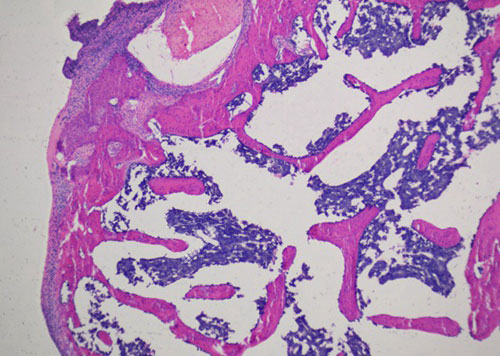

蘇木精-伊紅染色法 ( hematoxylin-eosin staining ),簡稱HE染色法,石蠟切片技術里常用的染色法之一,也可以用于未脫鈣骨硬組織切片。蘇木精染液為堿性,主要使細胞核內的染色質與胞質內的核糖體著紫藍色,伊紅為酸性染料,主要使細胞質和細胞外基質中的成分著紅色。HE染色法是組織學、胚胎學、病理學教學與科研中最基本、使用最廣泛的技術方法。

未脫鈣大鼠股骨HE染色